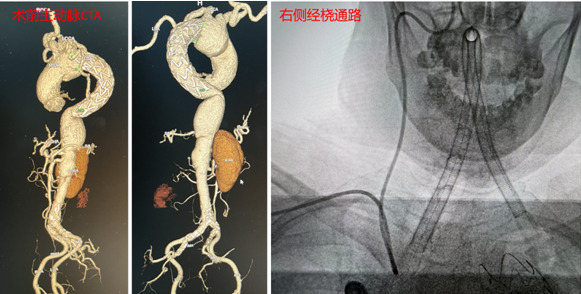

面对“开颅夹闭困难,经股动脉凶险”的双重困境,神经外科姜交德、卢韶华、陈远兵神经介入团队在反复研究患者影像资料后,提出了一个大胆的设想:放弃传统的“大腿”路径,改走“手腕”路径——经皮穿刺桡动脉行颅内动脉瘤栓塞术。

在与家属充分沟通并获得同意后,手术团队制定了周密的手术方案。手术中,专家凭借精湛的微导管超选技术在桡动脉建立通路,在复杂迂曲的血管中“翻山越岭”,精准抵达右侧颈内动脉,成功避免路经主动脉弓。面对宽颈动脉瘤的难题,团队巧妙运用支架辅助栓塞技术,将一根根弹簧圈严密填塞入动脉瘤囊内。

术后即刻造影显示,动脉瘤腔内血流消失,载瘤动脉通畅无阻,手术取得圆满成功,患者已康复出院。专家表示,此次手术的成功实施,不仅挽救了一条生命,更打破了复杂血管疾病患者介入治疗的入路局限,特别是对于合并有主动脉、髂股动脉疾患的患者,经桡动脉入路无疑提供了一条更安全、更高效的生命通道。